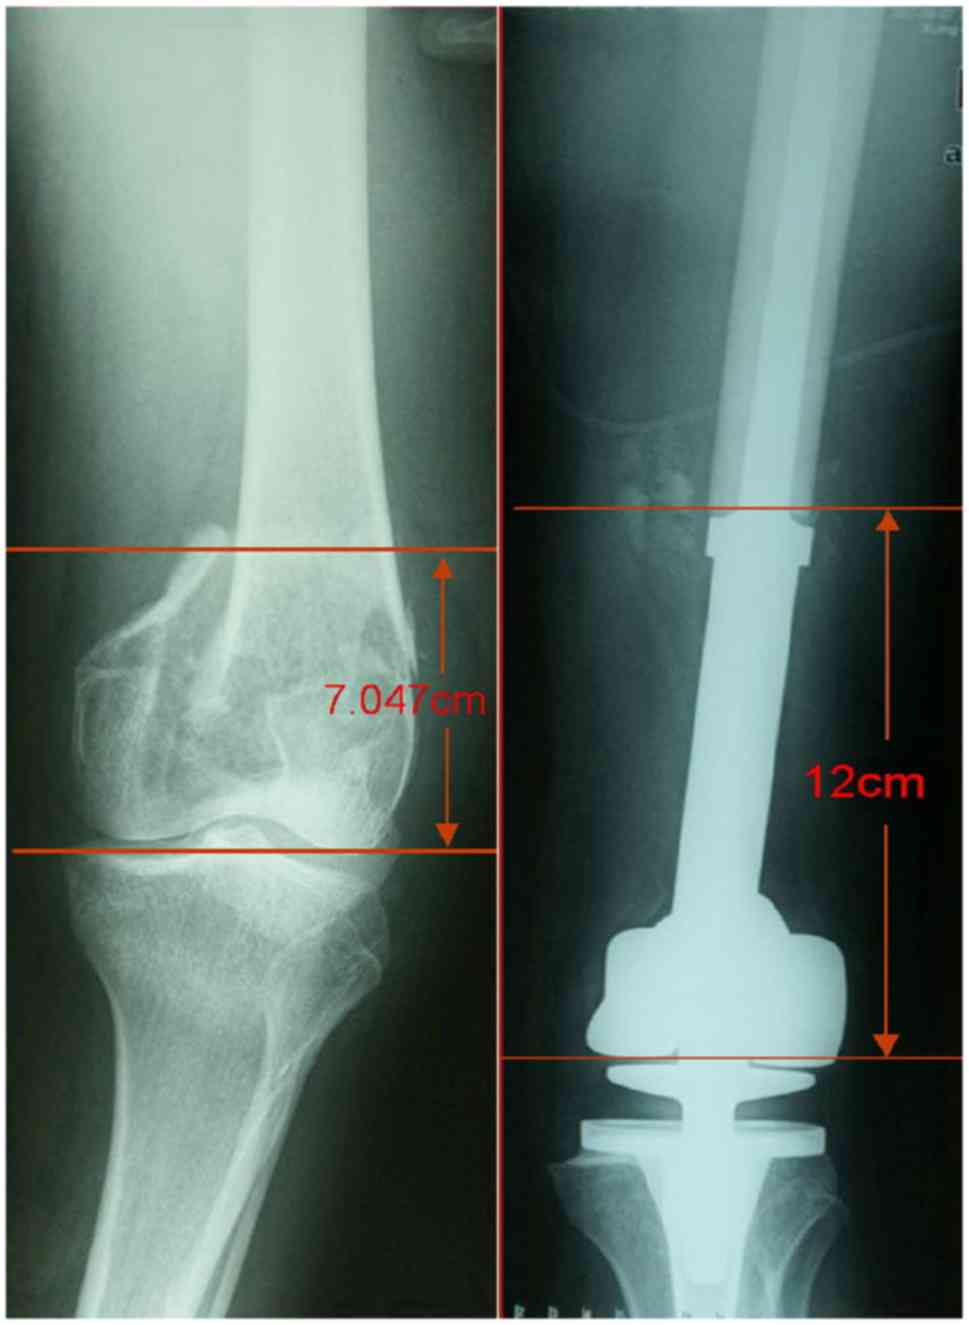

LIMB LENGTH DISCREPANCY 는 Malignant tumor resection 시에도 적용될 수 있는데 2cm 이내라면 추가적인 치료가 필요하지 않지만 2~5cm 의 경우 epiphysiodesis 가 필요하며, 5cm 이상 LLD 가 날 경우 rotationplasty, limb lengthening expendable prosthesis, staged lengthening 등을 시행할 수 있습니다.